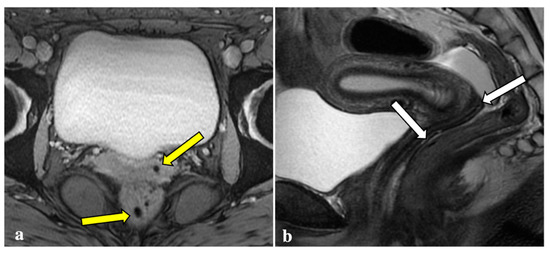

3.2. MRI Findings